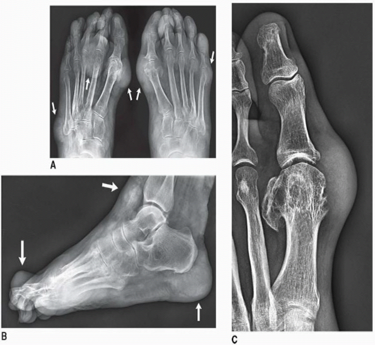

Metabolic Arthropathies

Many diseases involving the metabolism of the body can present themselves with joint manifestations. These include Hemochromatosis, Alkaptonuria, Acromegaly, Diabetes mellitus etc. Management requires control of the underlying disease.